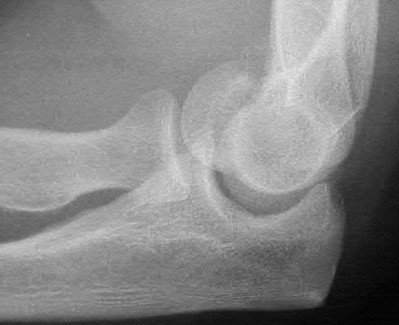

A patient has an elbow injury that includes a coronoid fracture, medial collateral ligament injury, and a radial head fracture. When is excision of the radial head without replacement indicated as definitive treatment for the radial head injury?

Excision is generally not indicated in this clinical scenario Corrent answer: 5

The injury likely represents a terrible triad injury. Restoration of the lateral column is required to restore valgus stability. A repaired or replaced radial head is also thought to be protective of the coronoid fracture repair. Therefore, excision is not indicated. Either radial head arthroplasty or open reduction and internal fixation would be indicated.